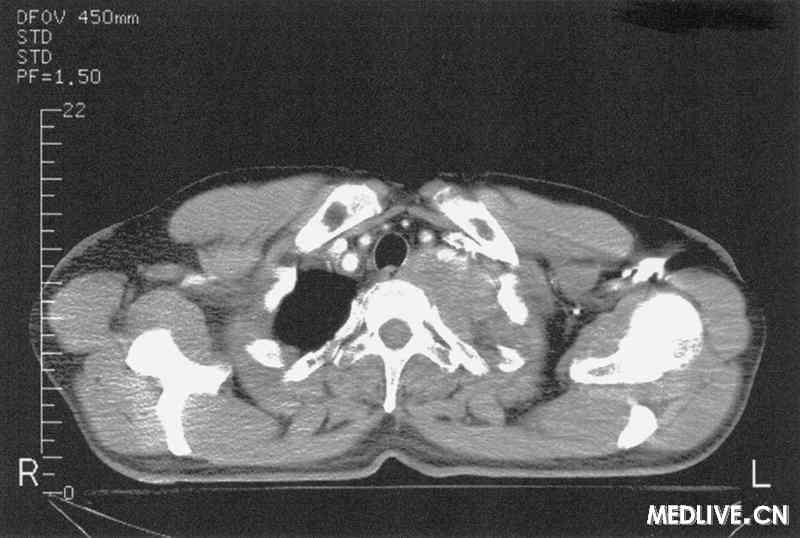

常见病因有肺癌、胸膜间皮瘤、乳腺癌、甲状腺癌、食管癌等,以肺癌最多见,尤其是肺尖癌或肺上沟癌,有时为肺尖部转移性癌。

肿瘤侵犯骨及通过胸腔入口的神经丛而引起症状,若第1、2肋骨被破坏,可有局部疼痛;臂神经丛受累时,可有上肢感觉或运动障碍;交感神经链被累及,可引起Horner综合征。